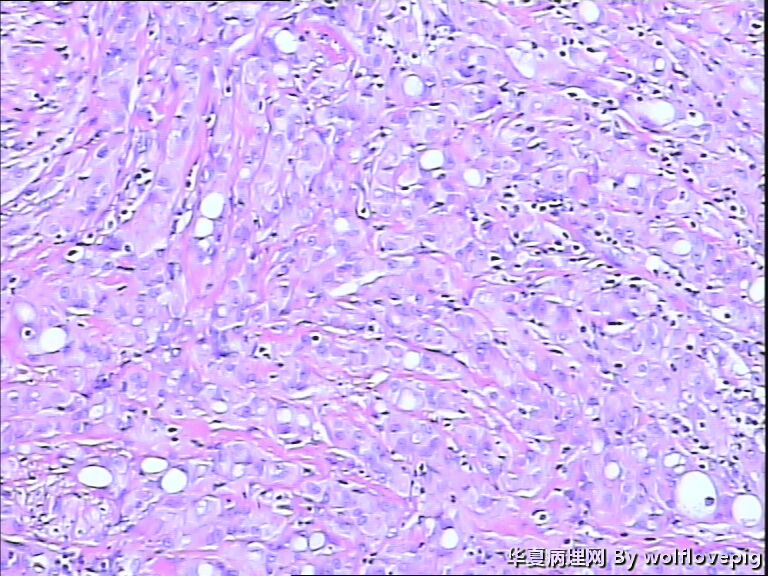

男,60y,左阴囊包块6月,位于附睾尾与睾丸之间,无粘连。灰白结节一个0.7*0.3*0.3,切面灰白、实体 、质韧。

图1

典型的腺瘤样瘤

同意腺瘤样瘤